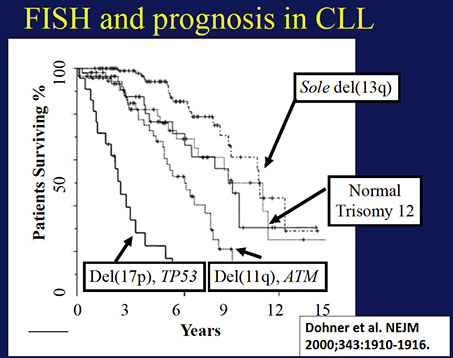

80% have FISH abnormality (50% have del13q14.3, 20% trisomy 12)

- BM involvement has poor px

- trisomy 12 has intermed px

Genes: MC abnormality is normal (1/2), then trisomy 12 (1/3, atypical cells, adverse px), then del13q14 (~1/4, has good px)

- FISH may have del 13q14 (>1/2), also tri 12, del(11q), del(14q), del(17p); 1/5 normal by FISH

-- del 13 and trisomy 12 have good px, del 11q and 17p have a poor px